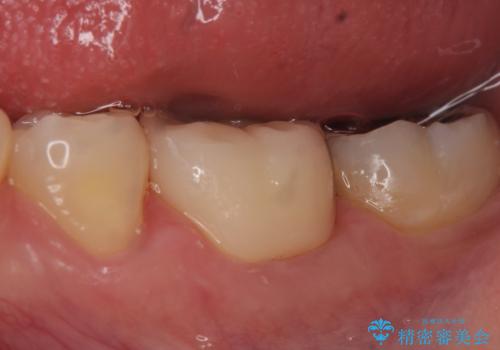

歯が折れた セラミックで綺麗に 30代女性